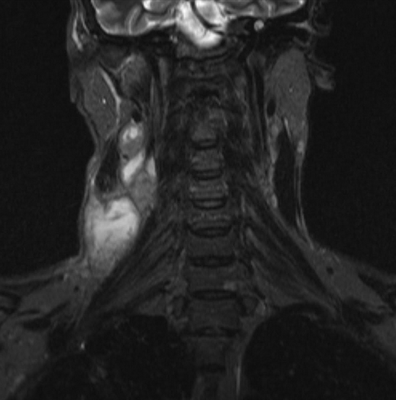

МРТ мягких тканей шеи что показывает

Воспалительные заболевания и объемные образования шеи часто встречаются в хирургической практике. Дифференциация патологий вызывает трудности из-за сложной анатомии рассматриваемой области и схожести клинических проявлений. МРТ позволяет получить подробные изображения мягкотканных и костных структур, опираясь на принцип магнитного резонанса. Компьютерная программа преобразует данные в серию срезов и формирует объемную картинку, которую можно увеличивать и рассматривать в любой плоскости. Толщину среза устанавливает врач в зависимости от предполагаемого диагноза, целей и задач исследования.

Магнитно-резонансная томография указанной области, вариант нормы

Что показывает МРТ мягких тканей шеи? На снимках видны:

добро- и злокачественные опухоли;

сосудистые мальформации, стеноз/дилатация артерий и вен, тромбообразование, отложение атеросклеротических бляшек;

лимфаденопатии при метастазах и воспалительной патологии;

ущемление нервных стволов;

послеоперационные осложнения и пр.

Результат МР-сканирования мягких тканей шеи